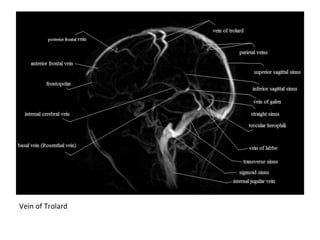

c) Superficial Cerebral Veins :

-The vein of Trolard connects superficial cortical

veins to the SSS

-The vein of Labbe drains the temporal

convexity into the transverse or sigmoid sinus